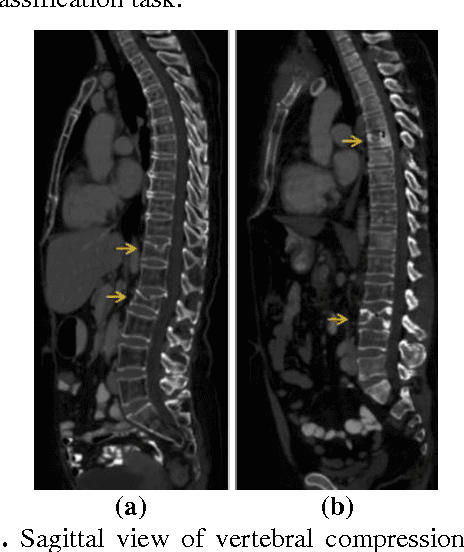

Classification of vertebral compression fractures (VCF) having osteoporotic or neoplastic origin is fundamental to the planning of treatment. We developed a fracture classification system by acquiring quantitative morphologic and bone density determinants of fracture progression through the use of automated measurements from longitudinal studies. A total of 250 CT studies were acquired for the task, each having previously identified VCFs with osteoporosis or neoplasm. Thirty-six features or each identified VCF were computed and classified using a committee of support vector machines. Ten-fold cross validation on 695 identified fractured vertebrae showed classification accuracies of 0.812, 0.665, and 0.820 for the measured, longitudinal, and combined feature sets respectively.